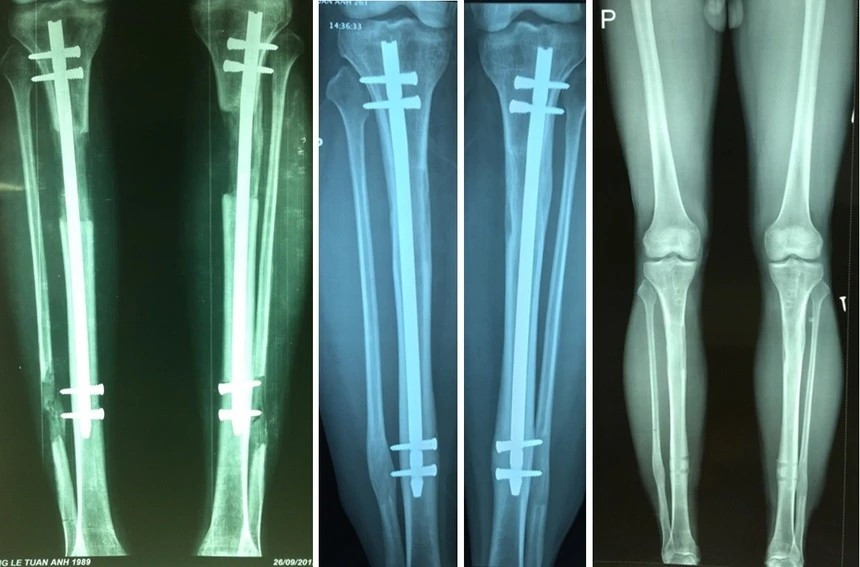

Theo vị chuyên gia, hiện nay, kỹ thuật kéo dài chi đã có nhiều cải tiến so với phương pháp cổ điển. Thay vì phải đeo khung kéo bên ngoài suốt nhiều tháng, bệnh nhân được cắt xương và đặt một đinh nội tủy vào trong xương. Sau đó, các đinh nhỏ xuyên qua hai đầu xương cố định phần chi cần kéo dài.

Khi đạt được chiều cao mong muốn, hệ thống khung sẽ được tháo bỏ, trong khi đinh nội tủy giữ vai trò cố định trong giai đoạn xương can chắc.

Phẫu thuật có thể thực hiện ở cẳng chân hoặc xương đùi. Nếu muốn kéo dài hơn, bệnh nhân có thể thực hiện tiếp giai đoạn thứ hai sau khi phần xương đầu tiên đã liền chắc. Xương kéo dài, nếu hồi phục đúng quy trình, có thể vận động bình thường, thậm chí chơi thể thao như đá bóng.

Hiện nay, các bác sĩ đã áp dụng phương pháp mới, với thời gian mang khung ít hơn, chỉ khoảng 3 tháng và sử dụng đinh nội tủy. Điều này không chỉ giúp các bệnh nhân thuận tiện hơn trong sinh hoạt cuộc sống mà giảm thiểu đáng kể nguy cơ nhiễm trùng chân đinh.